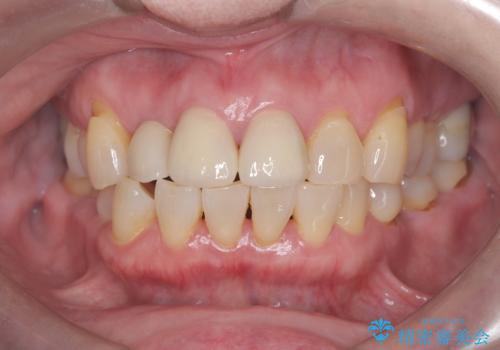

そのため今回は、右上2番を抜歯し、右上1番および左上1番をオールセラミッククラウンで審美的に修復しました。

矯正によって歯並びや咬み合わせを整えた後、必要に応じて歯の形や色を整えるためにホワイトニングやセラミック治療を行うことで、より自然で美しい仕上がりが期待できます。

治療期間も短く、抜歯からわずか3か月でオールセラミッククラウンを装着することができます。